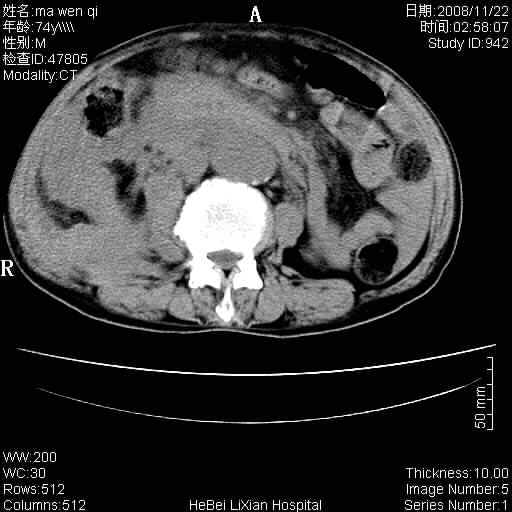

患者男 74岁.突然昏迷,休克6小时.血压70/30,头颅ct未见异常,既往体健.

补充病史,保留导尿10小时,尿袋内只有少许尿液,患者于住院后15小时后去世.

腹主动脉、双侧髂动脉夹层动脉瘤破裂出血进入腹腔。

1)考虑双侧髂动脉瘤并右侧动脉瘤破裂出血,右侧腹膜后及腹腔积血。2)双侧腹股沟疝。

1)考虑,腹主动脉、双侧髂动脉夹层动脉瘤破裂伴右侧腹膜后及腹腔积血。2)双侧腹股沟疝。